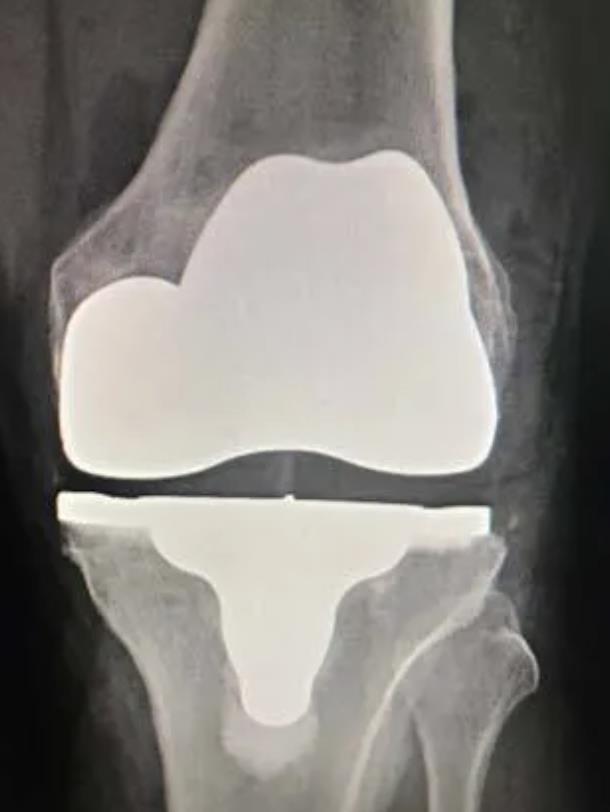

[Blocked from Release] iTotal Identity

https://upload.orthobullets.com/topic/423283/images/e1559d38-bbcb-42b5-b810-f57351f9e9f1_screenshot_2025-09-17_at_4.42.44_pm.jpg

• The iTotal Identity sets a new standard in knee replacement technology

• Patient-specific implants are designed around individual anatomy to promote physiologic kinematics, stability, and long-term joint health

• By leveraging advanced imaging technology and a proprietary database, iTotal Identity ensures that each implant is uniquely crafted to match the patient’s individual anatomy

• The platform personalizes implant geometry and streamlines intraoperative steps to support precise placement and efficient workflows